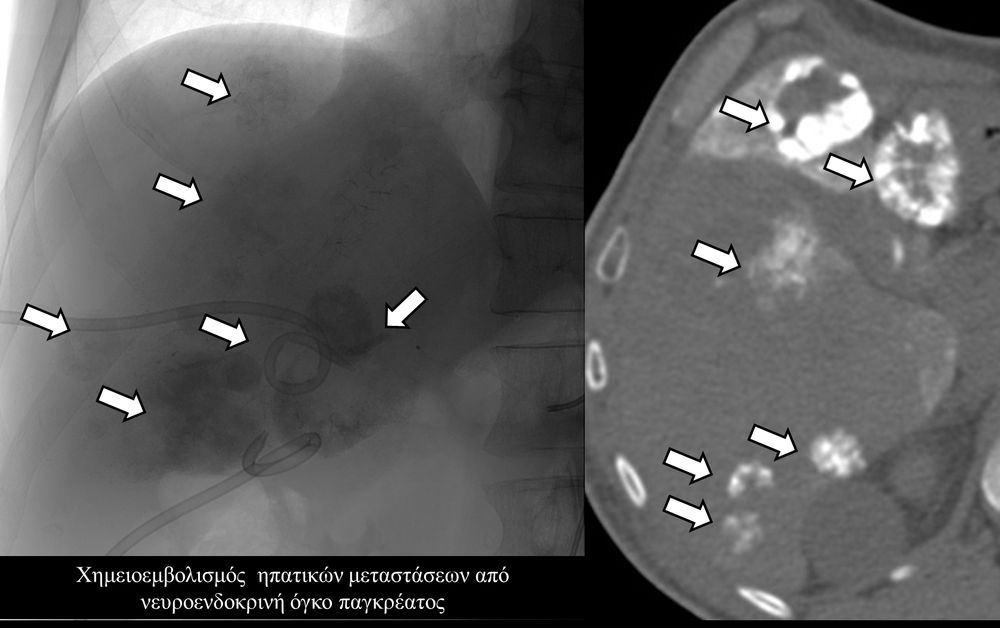

Ενδείκνυται επίσης σε ηπατικές μεταστάσεις από νευροενδοκρινείς όγκους, καρκίνο παχέος εντέρου και μελάνωμα, σε συνδυασμό με συστηματική χημειοθεραπεία της οποίας ενισχύει και βελτιώνει τα αποτελέσματα.